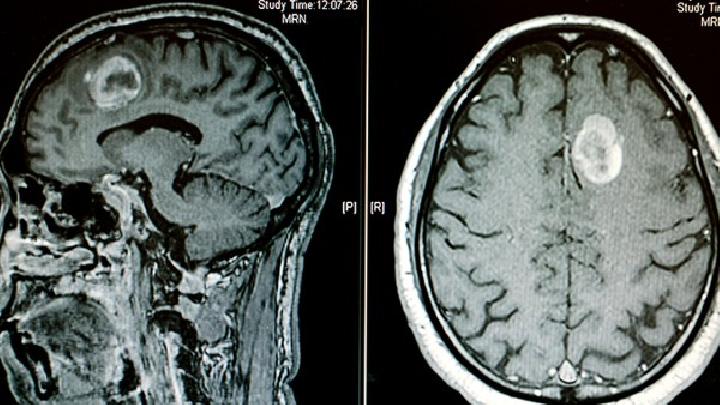

许多父母因为孩子而知道脑积水,很多人通过别人的经历而知道。更多的人通过宣传医学科普知识来了解它。脑积水已成为威胁婴幼儿的巨大隐患。人们需要深入了解它。然后简单说说脑积水的常规治疗。

脑积水的常规治疗是脑积水患者康复的必由之路。主要有手术治疗和药物治疗。这需要根据不同患者的身体状况进行选择。并非每个患者都适合手术治疗。同样,并非所有脑积水患者都能通过药物治疗康复。因此,我们需要仔细选择。

在过去的20年里,世界各地的学者对该疾病的治疗进行了大量的研究,但仍没有突破。手术治疗是其研究的主要途径,总结如下: